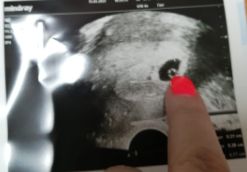

21 дпп первое УЗИ

Изображение

Сегодня была на узи, сказали видно одного. ПЯ 12мм, ЖМ 3,1мм. Через неделю опять на узи , надеюсь услышать Сб